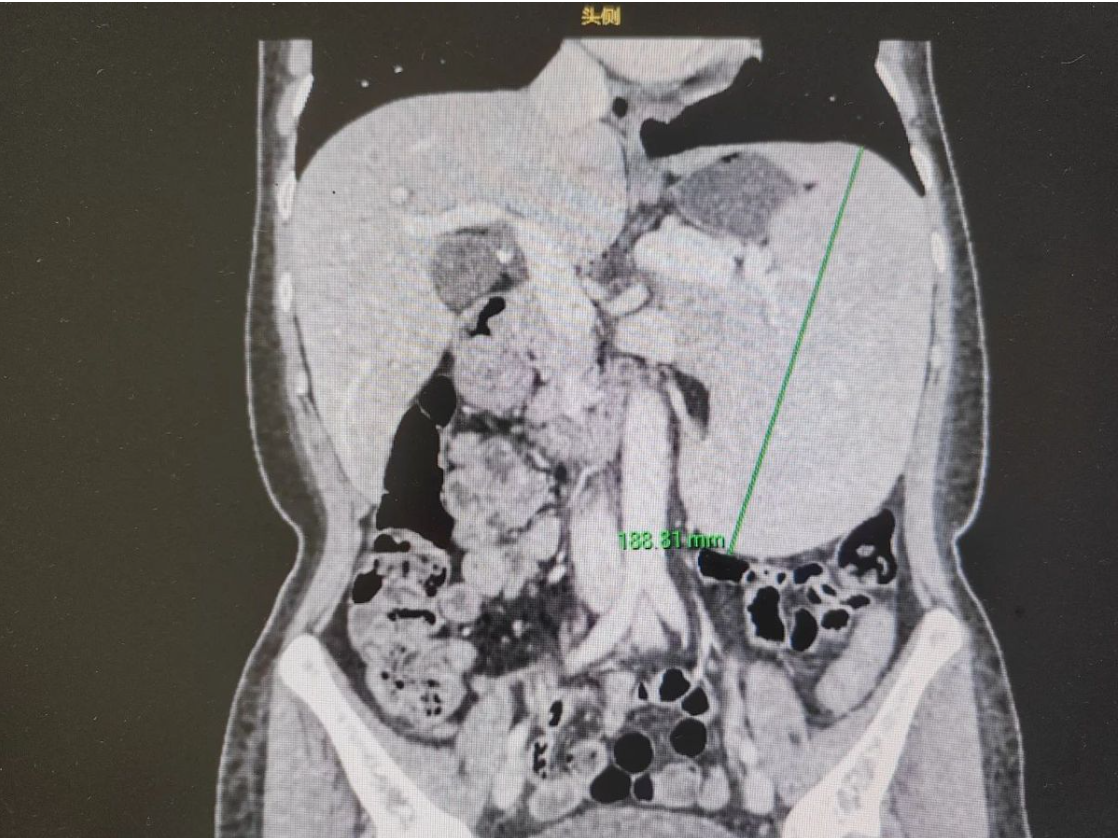

当林树文主任的腹腔镜探入患者体腔时,手术室骤然陷入沉寂——膨胀至18cm的畸形脾脏如定时炸弹盘踞腹腔,与膈肌、胃壁形成的致密粘连组织像蛛网般包裹着重要血管。这个被地中海贫血摧毁的器官,此刻正以188mmx176mmx102mm的骇人体积,挑战着现代微创外科的精准极限。

44岁患者刘某某的诊疗档案记载着残酷病程:血红蛋白值暴跌至62g/L的危急数据,胆囊结石与脾静脉扩张的多重并发症,以及持续两年夜间痛醒的生存炼狱。滨海湾中心医院MDT团队在三维影像重建中发现,患者脾脏已突破正常体积6倍,脆弱的器官包膜随时可能破裂引发致死性大出血。"这不是常规的脏器切除,而是在血管迷宫中拆解炸弹。"主刀医生在术前讨论中强调,传统开腹手术可能引发灾难性粘连出血,而腹腔镜手术需在厘米级操作空间完成毫米级血管离断。